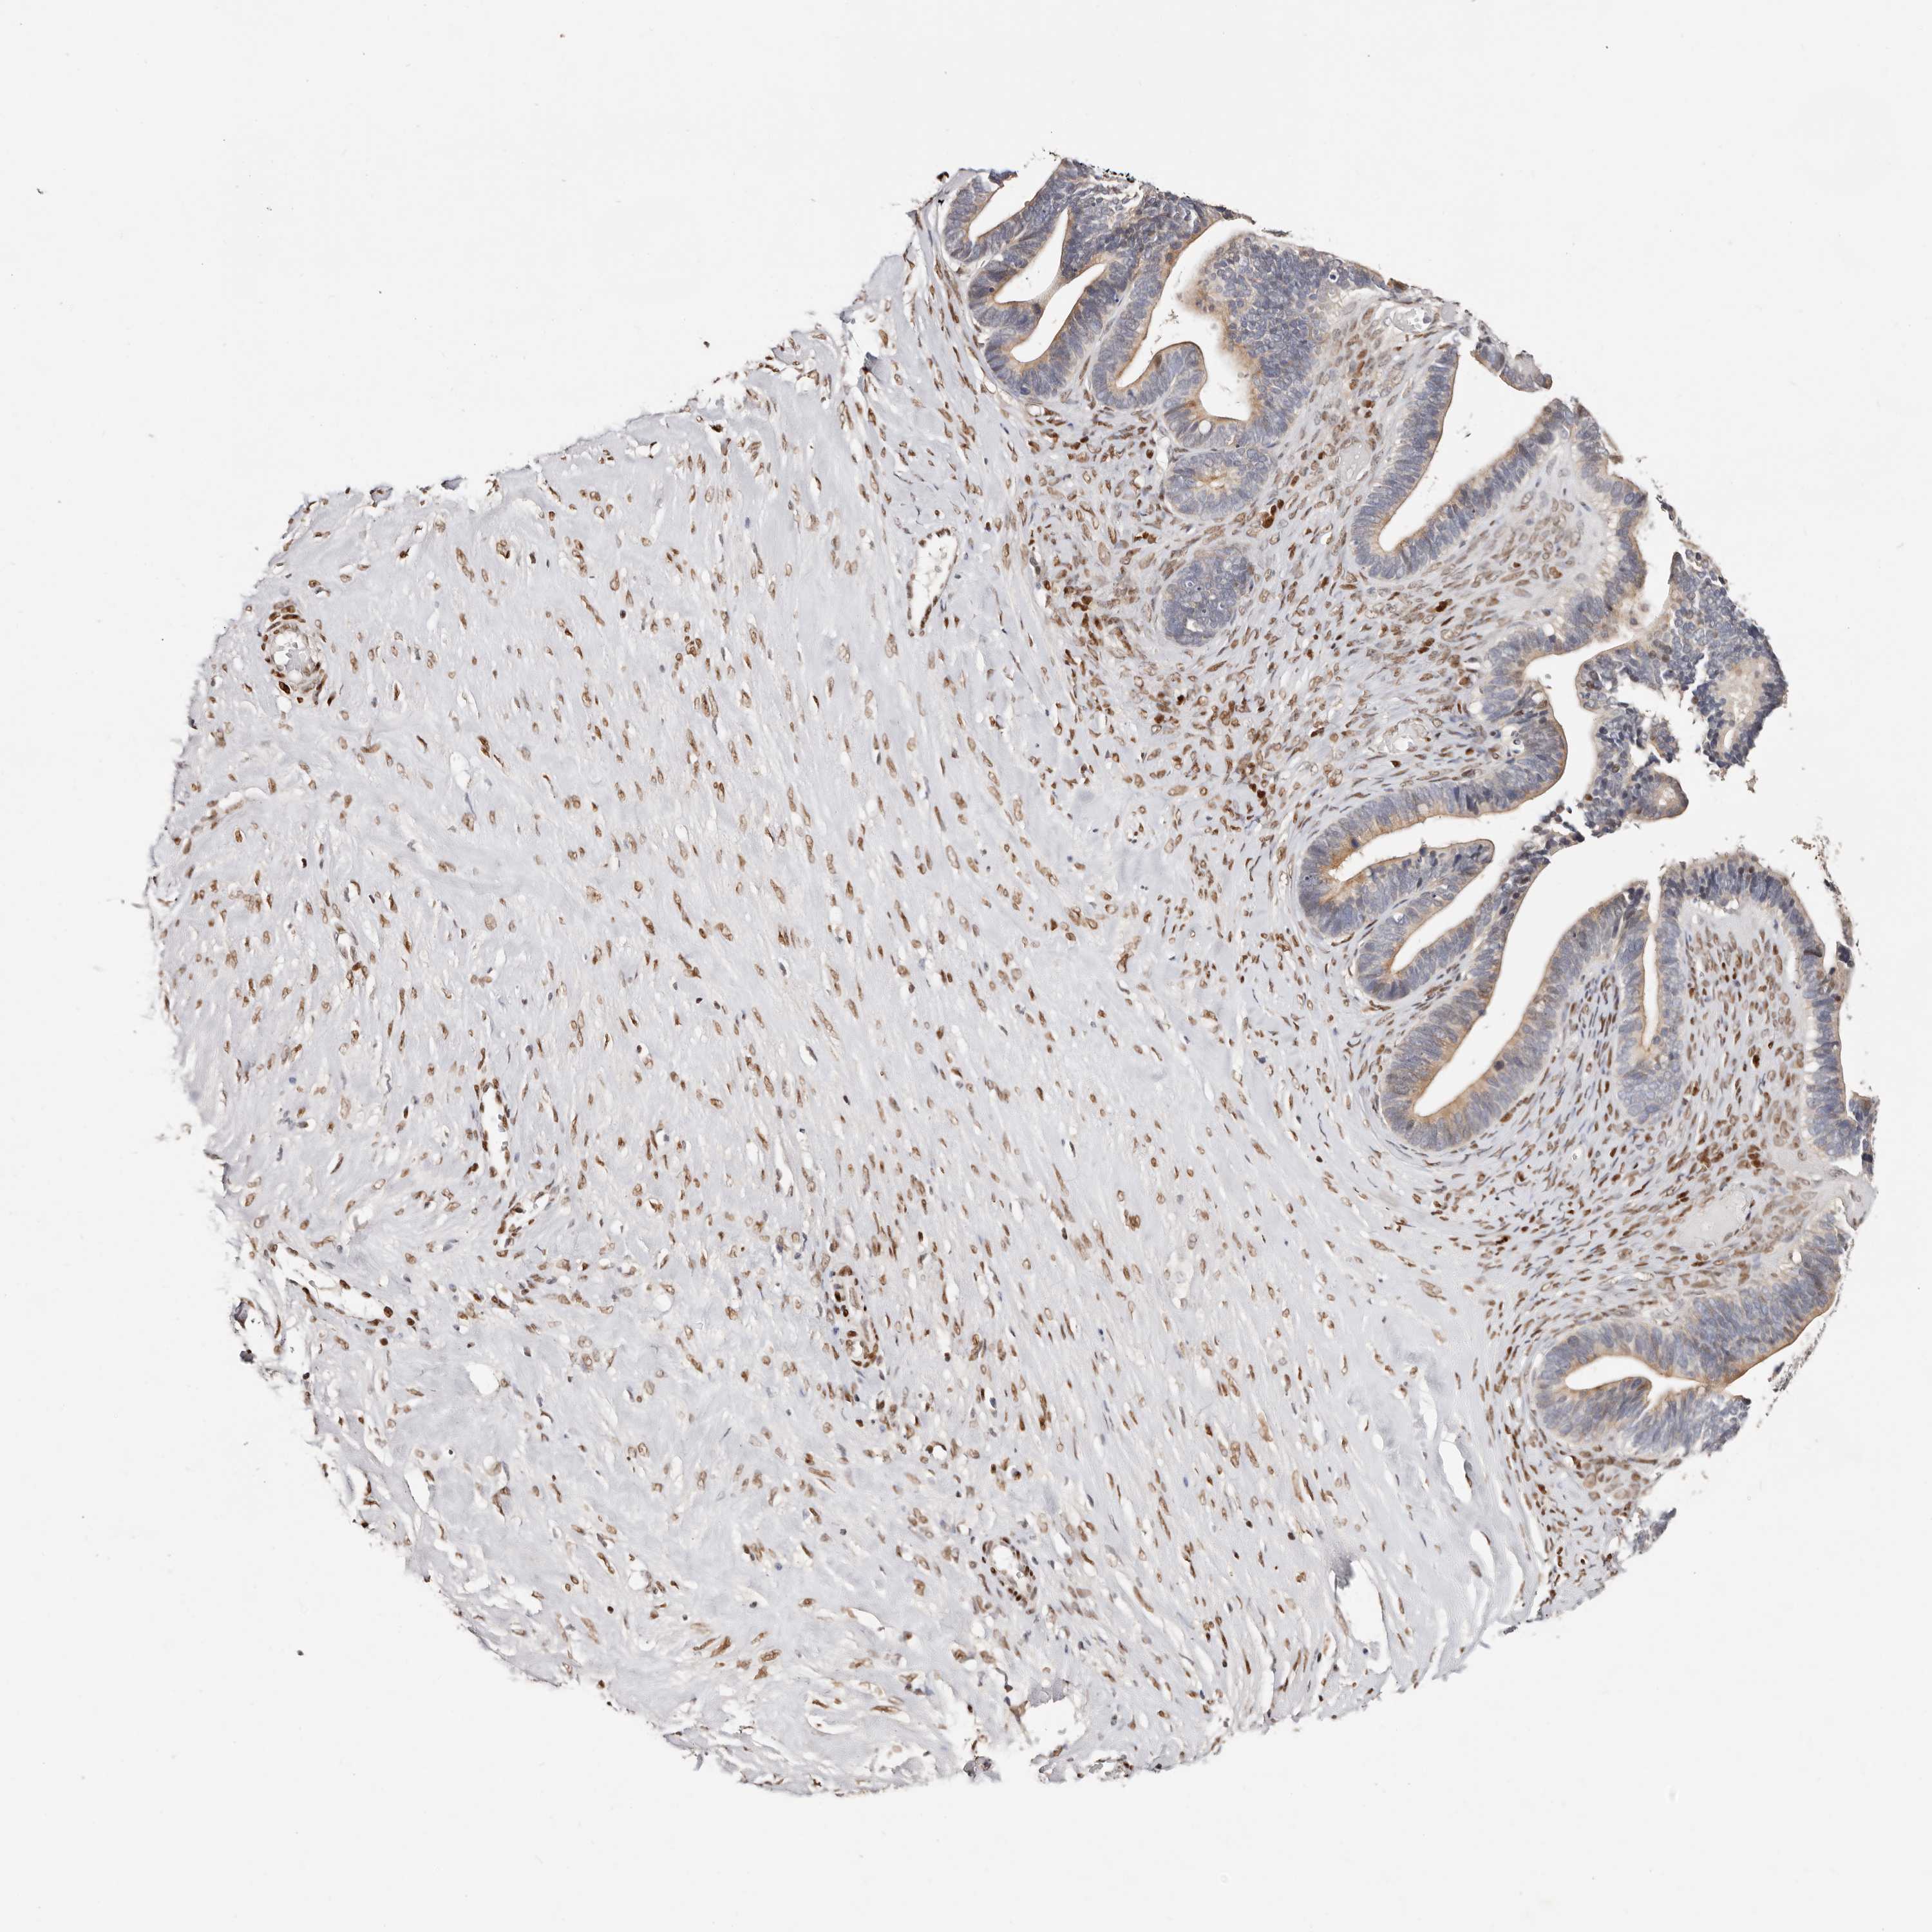

OVARIAN CANCER - Protein expressioni

A mouse-over function shows sample information and annotation data. Click on an image to view it in a full screen mode. Samples can be filtered based on level of antibody staining by selecting one or several of the following categories: high, medium, low and not detected. The assay and annotation is described here.

Note that samples used for immunohistochemistry by the Human Protein Atlas do not correspond to samples in the TCGA dataset.

Antibody stainingi

Antibody staining in the annotated cell types in the current human tissue is reported as not detected, low, medium, or high, based on conventional immunohistochemistry profiling in selected tissues. This score is based on the combination of the staining intensity and fraction of stained cells.

Each image is clickable and will lead to virtual microscopy that enables deeper exploration of all samples and also displays staining intensity scores, fraction scores and subcellular localization as well as patient and tissue information for each sample.

Antibody HPA030142

Antibody HPA030143

Cystadenocarcinoma, serous, NOS

Carcinoma, endometroid

Cystadenocarcinoma, mucinous, NOS

Carcinoma, NOS